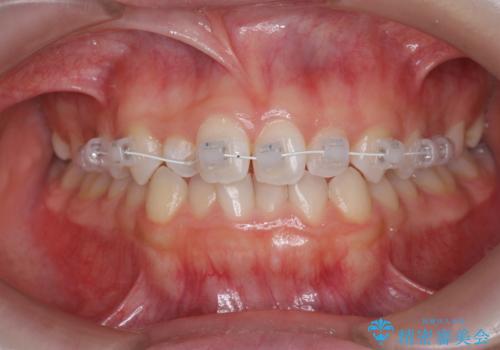

前歯のガタつき・ねじれを治すマウスピース矯正

- 前歯のねじれ、ガタつきを改善し綺麗な歯並びにしたいと希望され来院されました。

マウスピース矯正インビザラインによる矯正治療を計画しますが、マウスピース矯正で治りにくい歯のねじれを事前にワイヤー矯正でしっかりとなおしておくことで矯正治療期間の短縮できるような治療計画を立てます。

マウスピース矯正を始める前にワイヤー部分矯正を行ったことで改善のしにくい歯のねじれをしっかりと治すことができました。